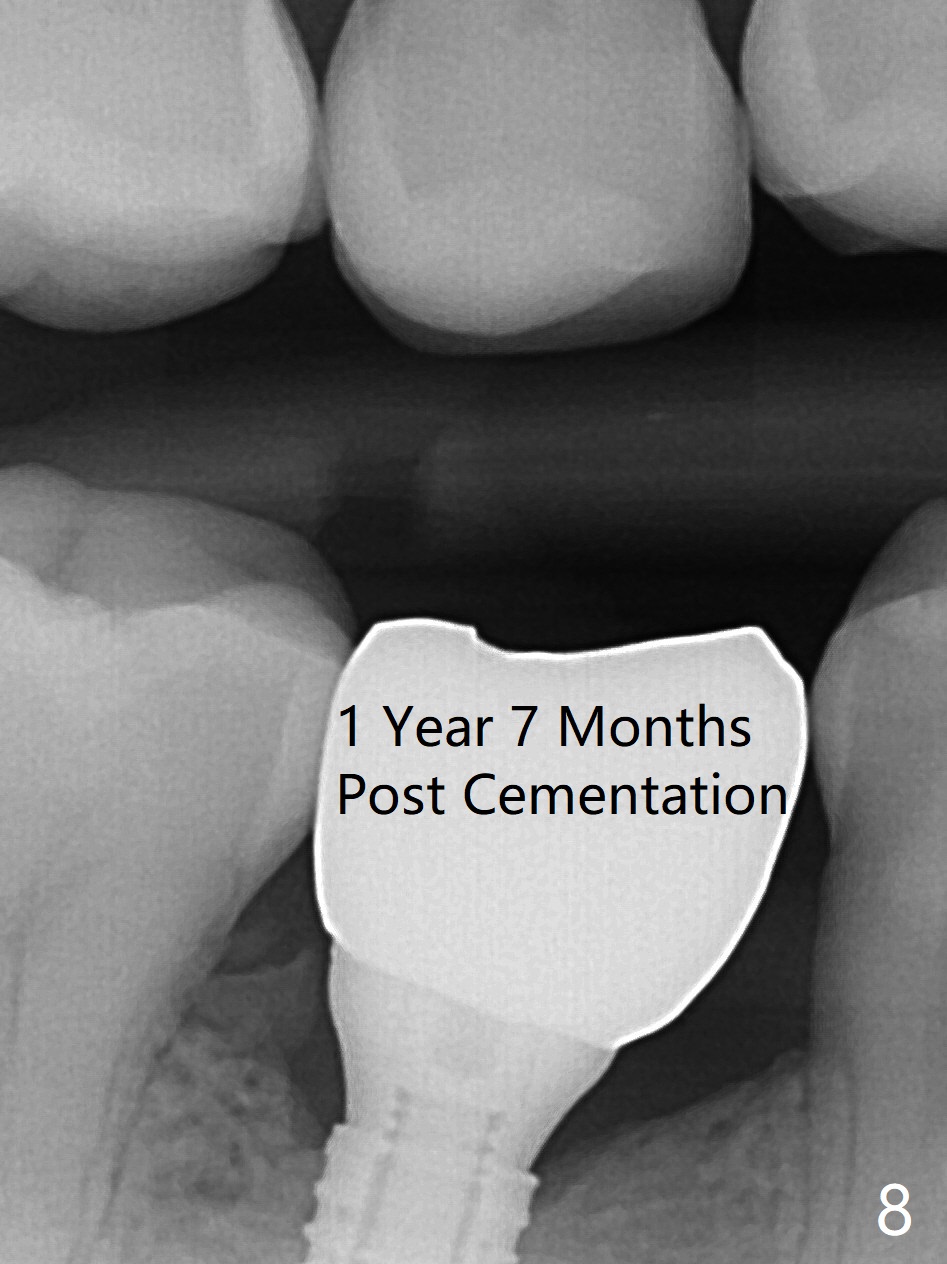

The base of the edentulous ridge at #29 looks wide (Fig.1), but the most coronal portion is the thin soft tissue (Fig.2).  It appears that there has been bone resorption since extraction.  The initial osteotomy depth is 11.5 mm (Fig.3).  Since the Mental Loop seems to be nearby, the depth of subsequent osteotomy (3 mm) remains the same (Fig.4).  Although the final depth of osteotomy is 13 mm, the implant placed is short (3.8x11.5 mm, Fig.5,6), as compared to the immediate implant (3.8x18 mm) at the contralateral side (#20).  There is mild bone resorption mesially 4 months postop (Fig.7).  The crown is loose (poor osteotomy position, guide necessity) 7 months post cementation immediately prior to 18 cementation, although there is no gross bone losss 1 year 7 months post cementation (Fig.8).